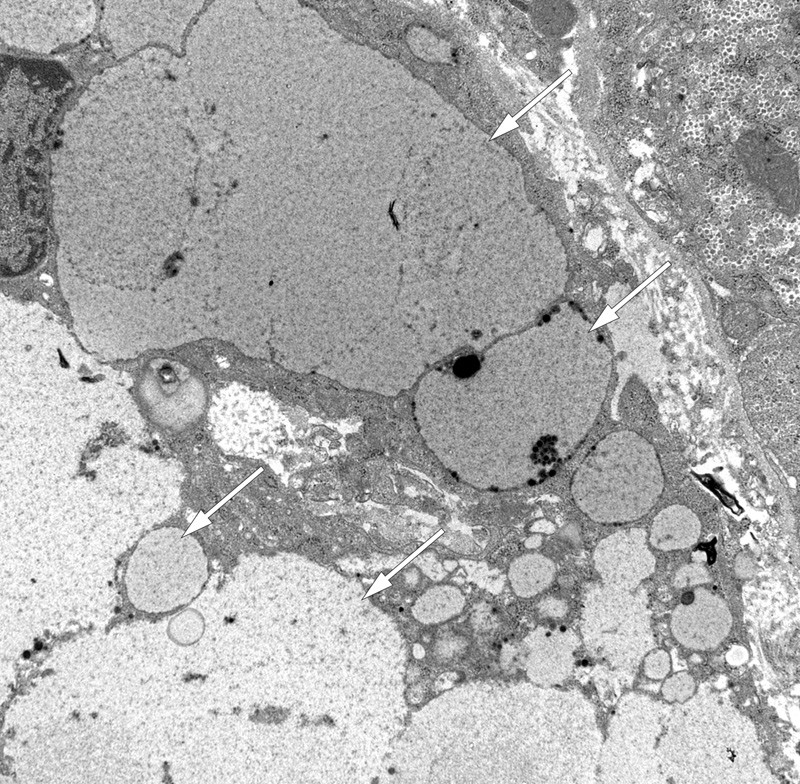

Transmisjonselektronmikroskopi viste grupper av fagocytterende celler med store intracellulære vakuoler med jevnt fingranulert innhold med lav elektrontetthet (fig 4). I hepatocyttene ble det påvist varierende forekomst av store lysosomer med fingranulert innhold med lav elektrontetthet, kombinert med små elektrontette korn og lipofuscinlignende materiale. I tillegg forelå det uspesifikke sekundære forandringer, inkludert lett kolestase og lette forandringer i mitokondriene med enkelte krystalline inklusjoner.